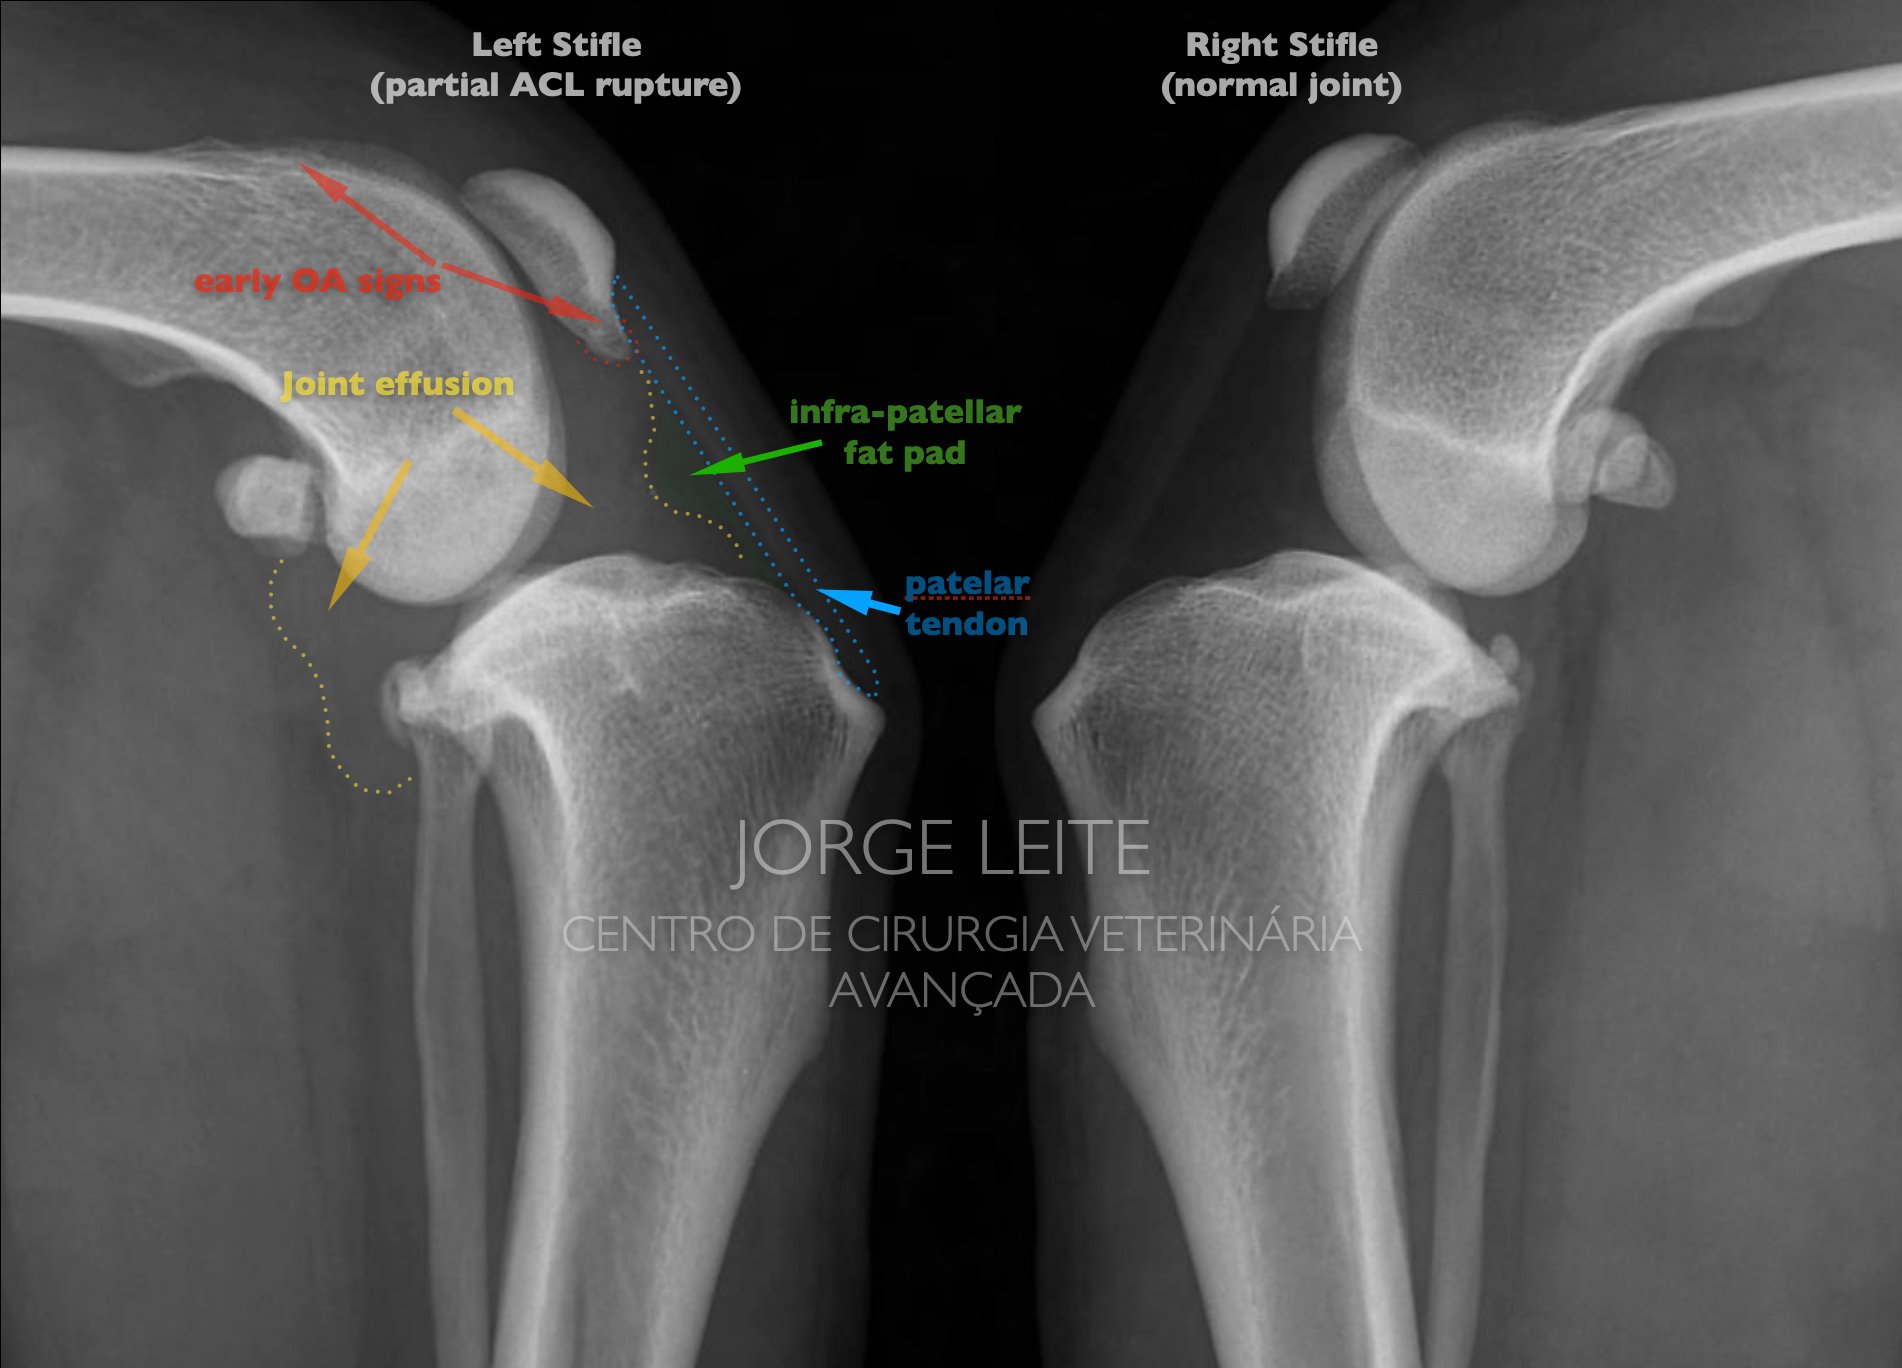

Pipa - rotura parcial de ligamento cruzado cranial

resultado 3 horas após TPLO por rotura parcial de ligamento cruzado cranial.